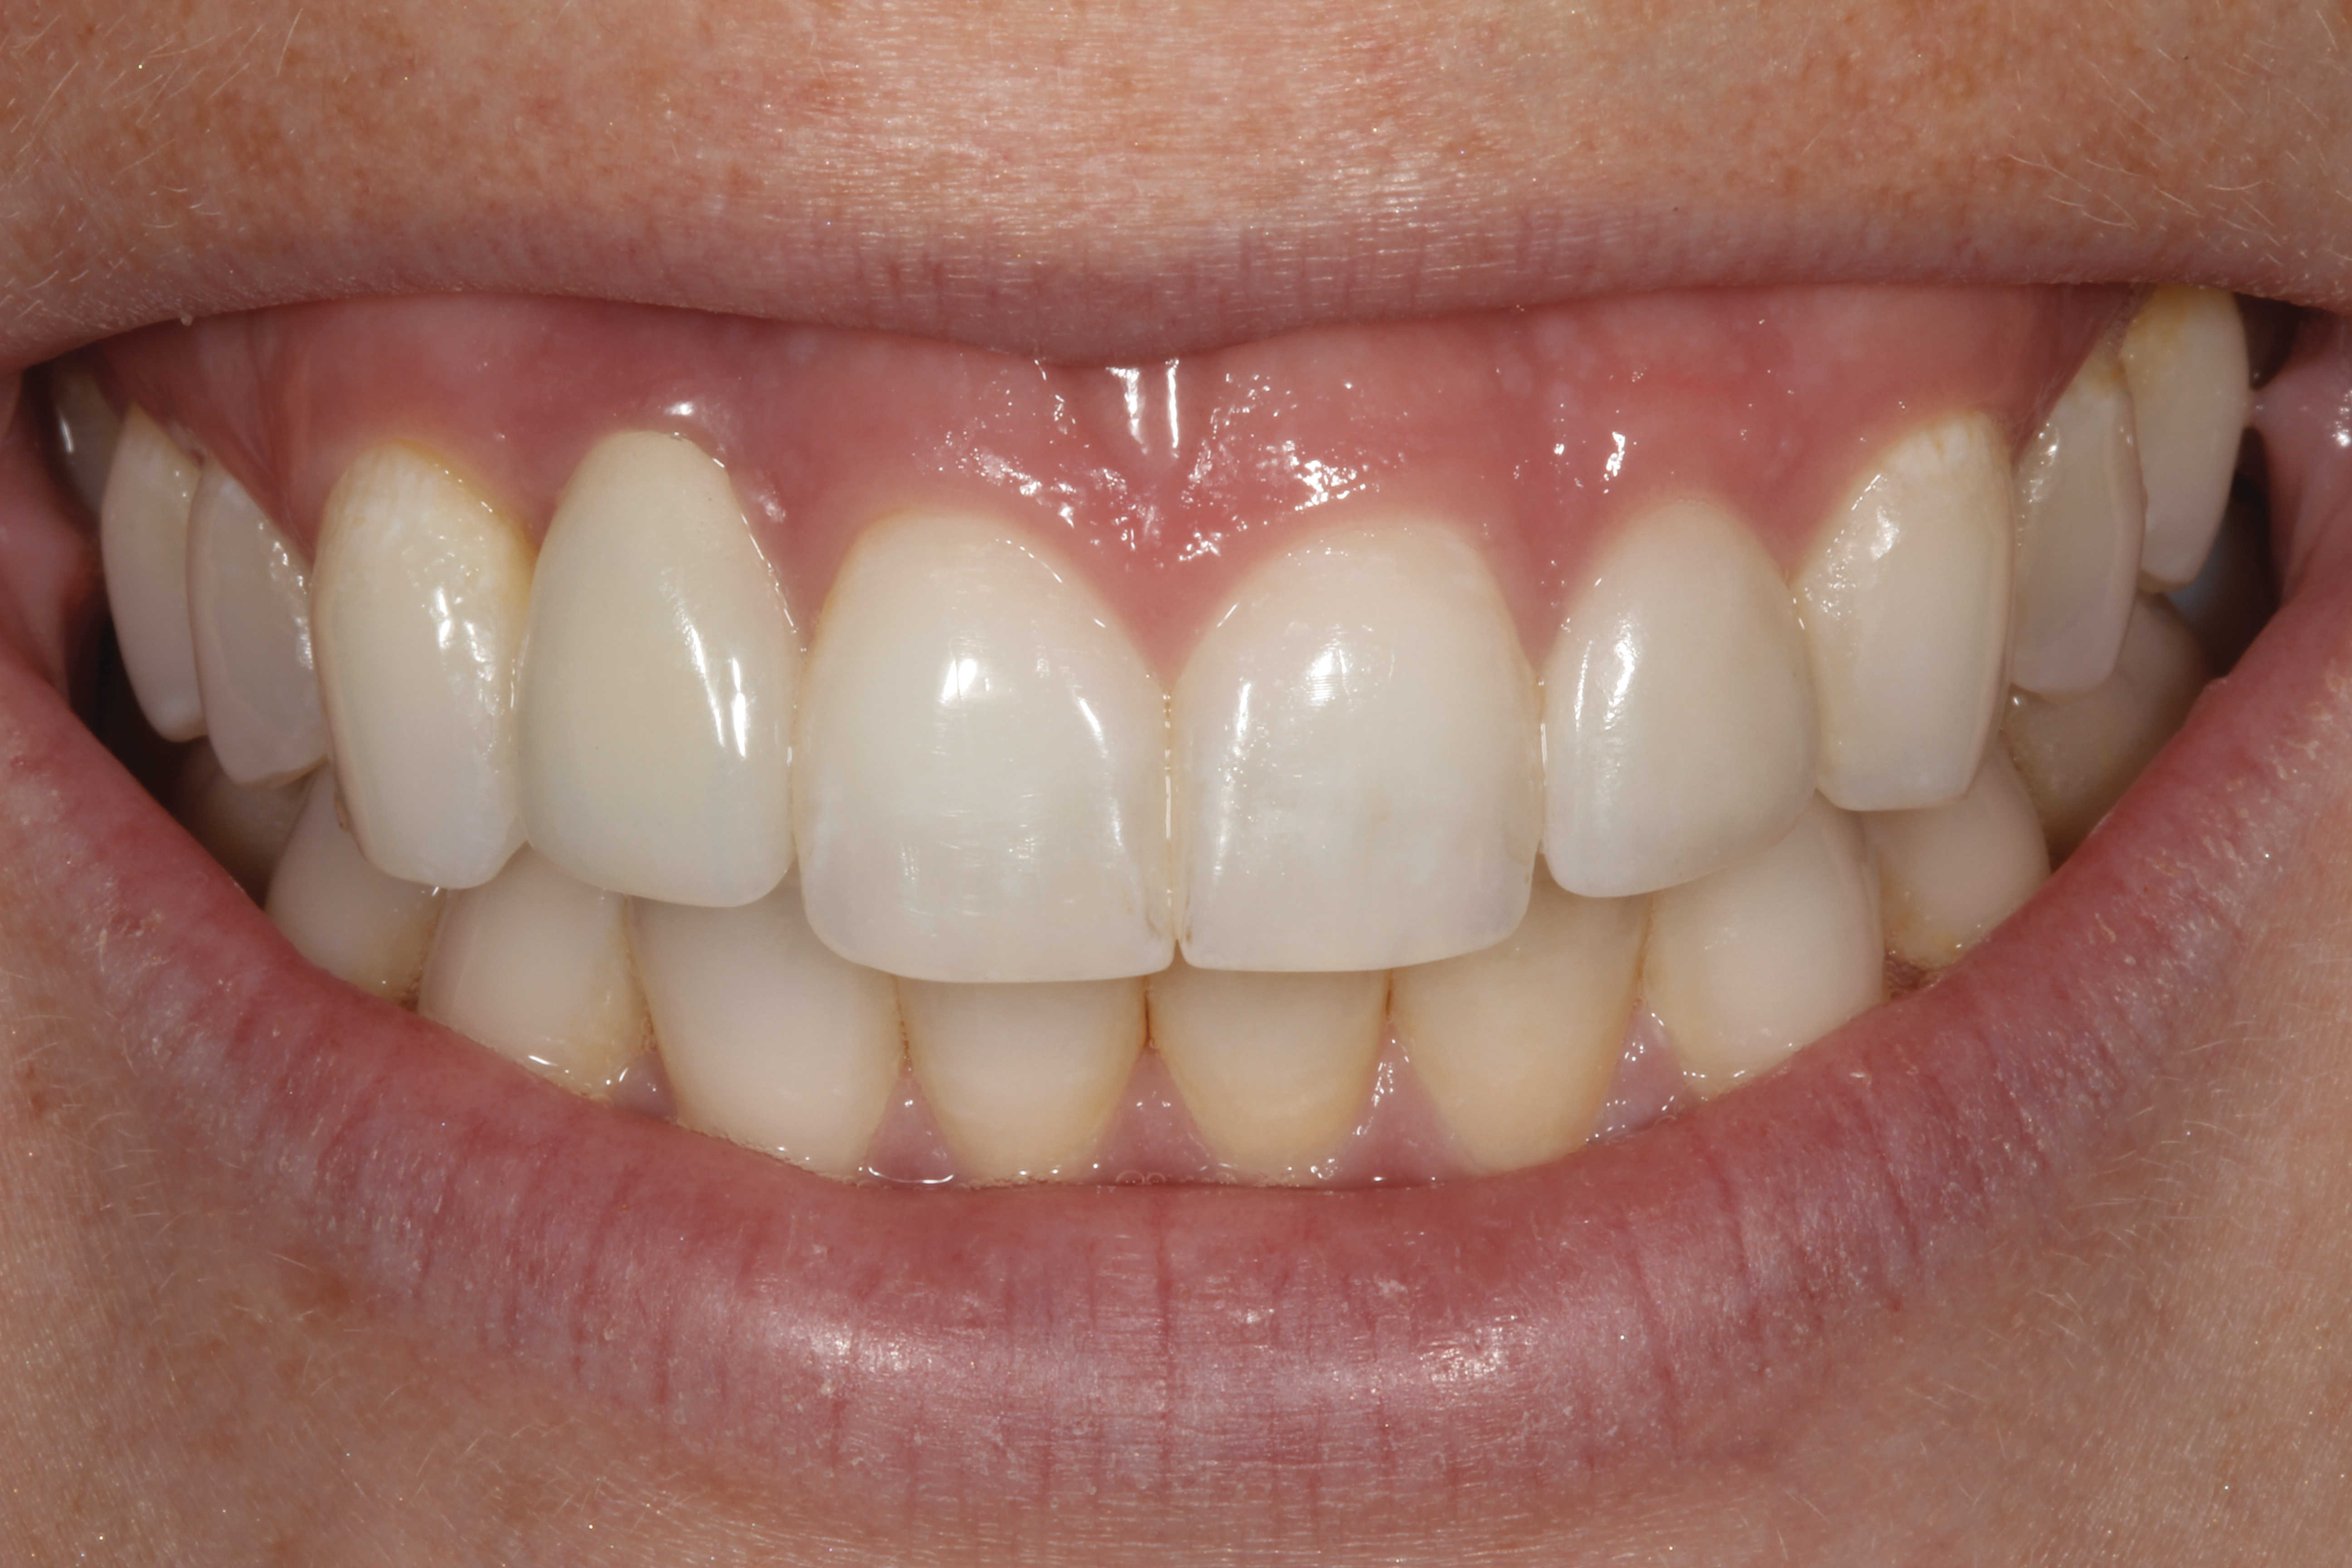

The following case report provides an example of this case scenario: A 28-year-old white female patient presented with her maxillary right lateral incisor significantly longer than the contralateral tooth following restoration of an existing crown that was 10 years old (Figure 3). The patient was dissatisfied with the esthetic appearance of the restoration due to the increased length, recession of the gingival tissues, and discoloration of the surrounding mucosa (Figure 4). Similar to case scenario No. 1, the first step in treatment was to decoronate the healthy implant by placing a flat surgical cover screw and employing a provisional resin-bonded-retained (RBR) prosthesis as a transitional fixed restoration (Figure 5 and Figure 6). The gingival augmentation in situ was allowed to take place for 2 to 3 weeks and was evaluated after that time (Figure 7).

Fig 3. A patient presented with a high smile line and midfacial recession of the maxillary right lateral incisor as evidenced by the increased tooth length compared with the contralateral lateral incisor.

Figure 3

Fig 4. Intraoral view of tooth No. 7 with the gingival zenith more apical than the adjacent central incisor and canine tooth.

Figure 4